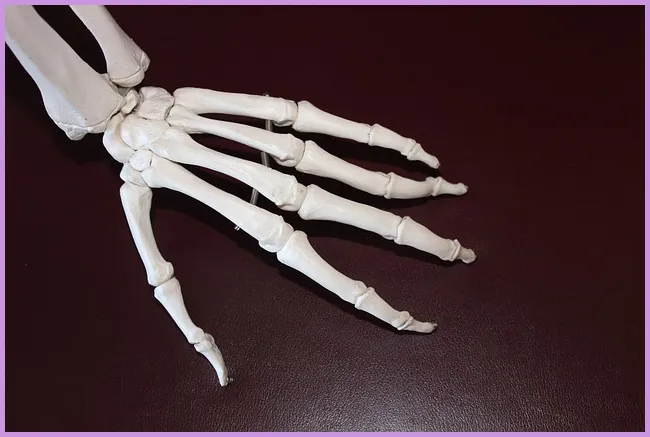

류마티스 관절염은 면역 시스템이 자신의 관절을 공격하여 염증을 발생시키는 자가면역 질환입니다. 이는 지속적인 통증과 불편함을 유발하며, 관절의 기능을 저하시킬 수 있습니다. 초기 단계에서는 일반적인 증상으로 시작하여 시간이 지남에 따라 악화될 수 있습니다. 이 질환은 주로 손, 발, 무릎과 같은 관절에 영향을 미치는 경향이 있습니다. 그렇다면 이 질환의 초기 증상은 무엇일까요?

- 관절 통증: 초기 단계에서 가장 흔한 증상입니다. 아침에 일어날 때 손이나 발의 관절이 뻣뻣하게 느껴질 수 있습니다.

- 부종: 관절이 붓는 것도 류마티스 관절염의 징후입니다. 이는 특히 손목과 손가락에서 두드러집니다.